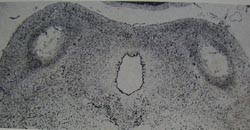

Figure xx shows damage in the inferior colliculi of a

human infant who died of suffocation. Thus damage

to the inferior colliculi caused by asphyxia at birth in

monkeys also happens in humans. Mirsky et al.

Damage of the inferior colliculi in a human infant (bottom) who died of suffocation. -->

From Leech & Alvord (1977) with permission from the American Medical Association.